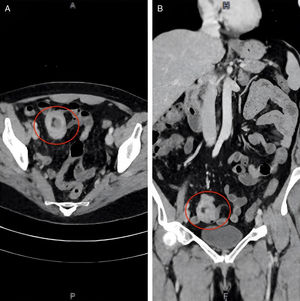

A su llegada al servicio de urgencias se encontró estable, signos vitales dentro de parámetros normales, refirió cuadro clínico caracterizado por dolor abdominal en fosa iliaca derecha, sin irradiaciones, intensidad moderada, náusea, vómito de contenido gástrico y hematoquecia. Recibió tratamiento sintomático, sin mejoría clínica. A la exploración física se encontró abdomen sin alteraciones. En sus estudios de laboratorio destacaba anemia microcítica hipocrómica, resto dentro de parámetros normales. Se realizó tomografía de abdomen con contraste intravenoso con reporte de oclusión intestinal con imagen de intususcepción a nivel de íleon terminal y un pólipo en su interior (fig. 1A [corte axial] y 1B [corte coronal]). Como parte del abordaje, se realizó enteroscopia retrógrada con monobalón que reportó: lesión exofítica que abarcó más del 80% del lumen, cubierta de fibrina, con pérdida del patrón mucoso y vascular, indurada y friable (fig. 2A y 2B); se realizó toma de biopsias y se marcó la zona adyacente con tinta china, el reporte histopatológico se recibió posteriormente, siendo compatible con adenocarcinoma primario de íleon (fig. 3A, [asterisco], 3B y 3C); se realizaron estudios de extensión documentándose captación solo a este nivel. Como parte del tratamiento se realizó abordaje laparoscópico con resección intestinal guiada y marcada previamente con tinta china, posteriormente anastomosis laterolateral mecánica extracorpórea, reportando tumoración de 2x2cm sin invasión a estructuras adyacentes con márgenes libres de malignidad. La paciente fue valorada por oncología y posteriormente dada de alta sin eventualidades. Actualmente se encuentra asintomática y con buena evolución, el seguimiento será por oncología.